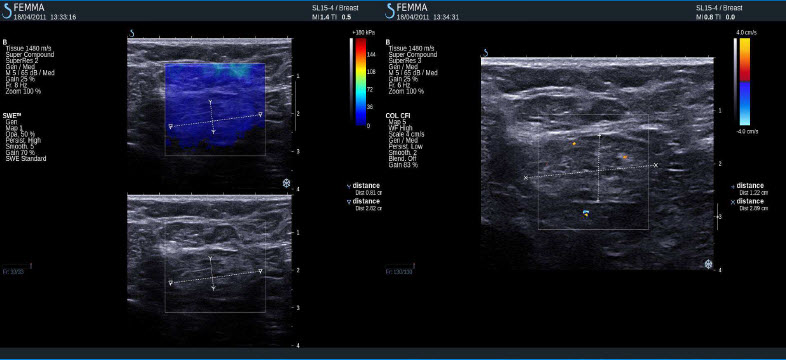

Fibroadenom

Pozitivní výsledky elastografie / histologicky potvrzená malignita